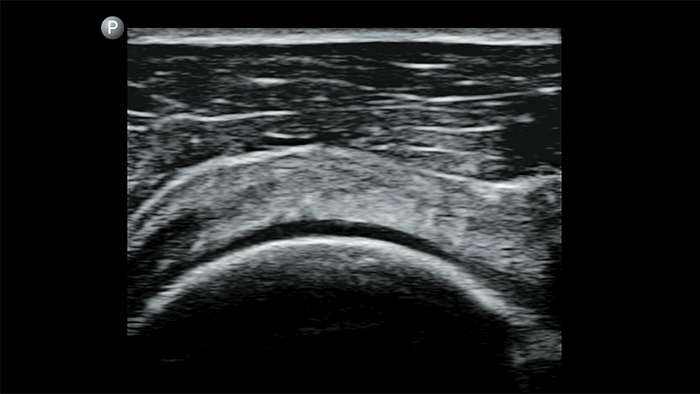

Ultrasound exams can improve your ability to identify and successfully treat skin abscesses.

POC ultrasound for soft tissue